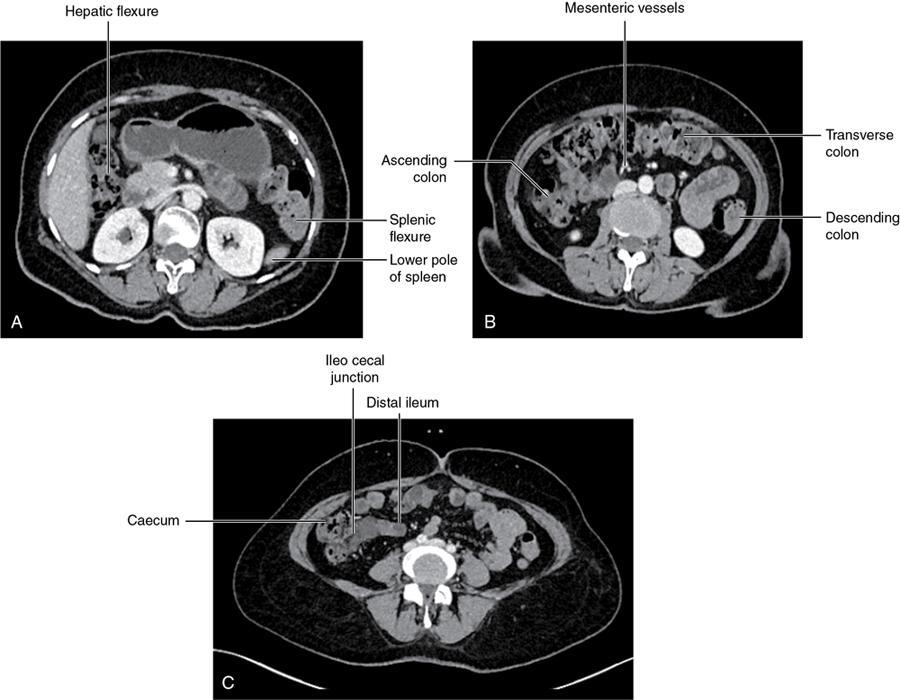

CROSS SECTIONAL ANATOMY OF ABDOMEN Satya Jha NORMAL ANATOMY OF ABDOMEN AND PELVIS Amandeep Singh The two major surfaces: The anterior and posterior layers of the coronary ligament converge on bare area (not covered by peritoneum). Its right and left margins form the right and left triangular ligaments. The right triangular ligament extends toward the diaphragm and separates right subphrenic space from right subhepatic space. The left triangular ligament gives tracts extending to the diaphragm and falciform ligament and does not compartmentalize the left subphrenic space. Ligamentum teres or the obliterated umblical vein is contained in falciform ligament which attaches the liver to anterior abdominal wall. The main portal vein, the proper hepatic artery and the common bile duct are contained within investing peritoneal folds of hepatoduodenal ligament at the porta hepatis (Fig. 7.2.2.1). Liver is divided into eight segments which are functionally independent and have their own vascular supply and biliary drainage. Arterial circulation: The branches of the hepatic artery accompanying the portal veins. Hepatic venous system: The right, middle, and left hepatic veins draining into IVC (Figs. 7.2.2.2 and 7.2.2.3). The gallbladder is a blind pear-shaped muscular membranous sac which is an embryologic derivative of the foregut, is a pouch lying along the undersurface of the liver. The gallbladder fossa is located in the plane of the interlobar fissure, which lies between the right and left hepatic lobes. Its major function is to store and concentrate bile which is produced by the liver. It measures approximately 4 cm in diameter when it is normally distended. Gallbladder is a smaller tubular structure in contracted state. The normal gallbladder wall thickness ranges from 1 to 3 mm. The gallbladder is divided into the fundus, body and neck. Infundibulum is present in the region of neck of the gallbladder, which is called the Hartmann pouch, where gallstones are usually impacted. Intrahepatic biliary radicles (IHBRs) scattered throughout the liver get confluent towards the hilum. They unite to form the right and left main hepatic ducts which further unite to form common hepatic duct (CHD) at the hilum. Common bile duct is formed by the union of cystic duct with common hepatic duct. The main pancreatic duct is joined with the common bile duct to form the ampulla of Vater at the major duodenal papilla (Figs. 7.2.2.4 and 7.2.2.5). Pancreas is located in anterior pararenal space of retroperitoneum anterior to perirenal (Gerota’s) fascia and posterior to parietal peritoneum. It is divided into head, uncinate process, neck, body and tail from right to left. Pancreas lies anterior to portal vein, which marks the point of transition between the body and neck. The region between head of pancreas and second and third parts of duodenum is known as the pancreatic groove. In postnephrectomy cases or with agenesis of kidney or ectopic kidney, pancreas moves posteriorly to partially fill in the empty renal fossa; its soft tissue density should not be mistaken for recurrent tumour. It is located in the pancreatic groove and is bounded superiorly by the duodenal bulb, laterally by second portion of duodenum, inferiorly by third portion of duodenum, medially by superior mesenteric vein and anterior to inferior vena cava. It is a wedge or wedge shaped lying posterior to superior mesenteric artery and vein. It is an imaginary junction between the head and body and lies directly over the junction of the splenic vein and superior mesenteric vein. It is located posterior to the lesser sac and anterior to the aorta, left adrenal gland, left kidney, and renal vessels and runs obliquely upward to the left of the superior mesenteric vessels. It is situated median to the colonic flexure and anterior to the left kidney. It is located in close proximity to the splenic hilum without a notable relation with the body of pancreas. It is seen anterior to the left kidney and median to the colonic flexure. The distal part of the tail passes between the peritoneal layers of the splenorenal ligament (Fig. 7.2.2.6 and 7.2.2.7).